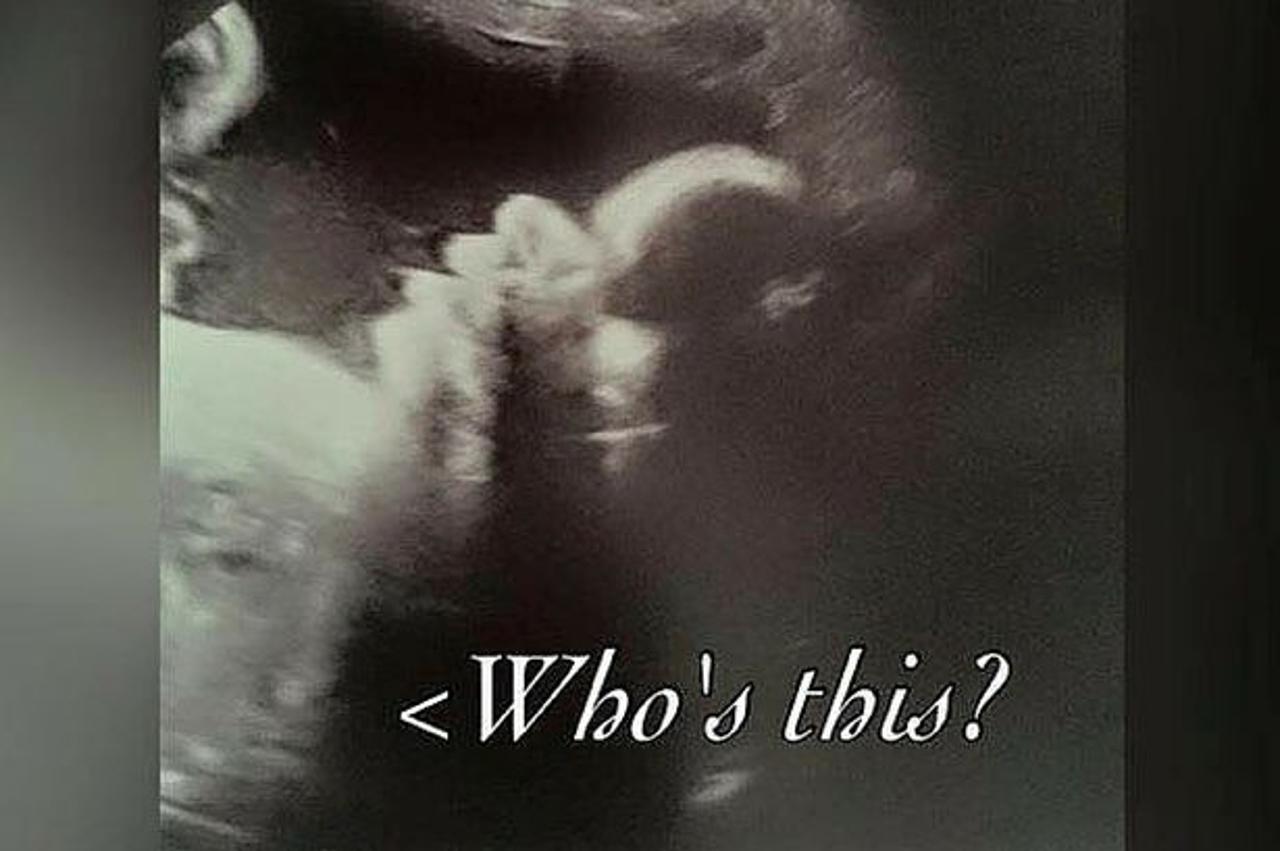

Slika s ultrazvuka iznenadila buduću majku: Ovo je najstrašnije što sam ikad vidjela

Trudnica Sharnii Turner bila je na ultrazvuku, no kada je vidjela kako joj dijete izgleda, prvo se prestrašila

Naime, glava djeteta izgleda poput mrtvačke lubanje pa je majka fotografiju odlučila podijeliti na Twitteru.

– Tehničar na ultrazvuku odlučio je napraviti snimku lica djeteta s prednje strane i to je najstrašnija stvar koju sam u životu vidjela – napisala je ona na Twitteru.

Ona se na takve neumjesne komentare nije obazirala već je samo objasnila da tako zapravo ljudska lubanja izgleda na snimkama ultrazvuka.